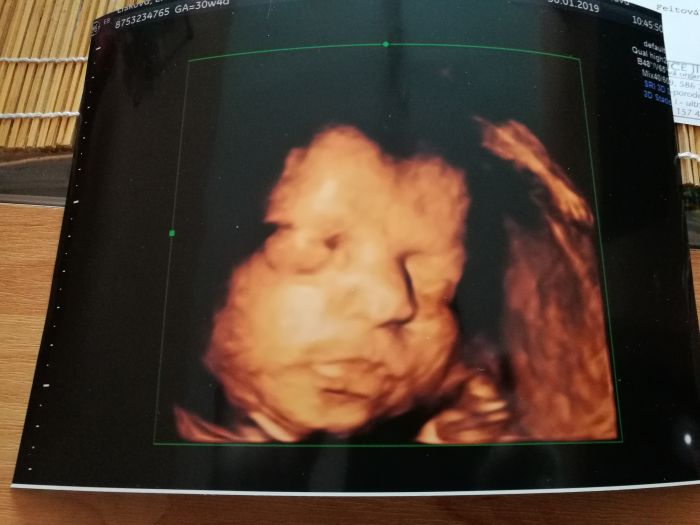

Ja mam dnes treti screening, tak se tesim az malou zase uvidim. Jestli bude dotecka, tak ji sem odpoledne dam.